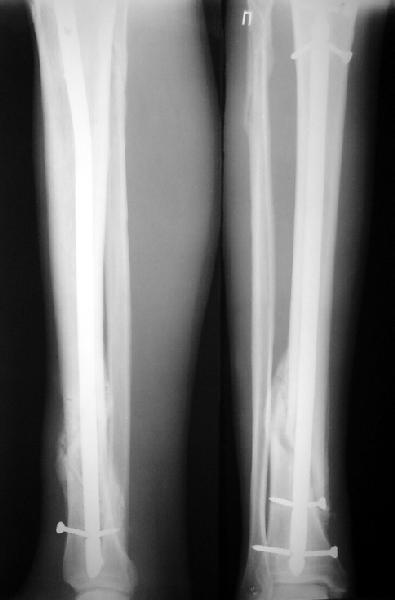

Как мне показать пример? Фото стоящего на одной оперированной конечности пациента? O! Пример, подвигнувший нас на некоторое изменение технологий. Пациент этот ходил с полной нагрузкой вопреки рекомендациям. В качестве подтверждения - сломанный проксимальный статический винт к 1 мес., а к 2 мес. - все остальные. Сейчас мы перешли на более fool-proof остесинтез.

На мой взгляд, на снимках, приведённых Вами - неправильно сростающийся перелом дистальной трети большеберцовой кости, состояние после остеосинтеза интрамедуллярным гвоздём.

Как Вы пишите снимок под номером 1 - менсяц после операции, под номером 2- два месяца после операции.

Вы не послали послеоперационный снимок, поэтому трудно судить о состоянии редукции после операции.

Установка с медиальной стороны гвоздя в области дистального фрагмента дополнительного шурупа помогло бы Вам репонировать и удержать перелом в анатомическом положении, предотвратило варусную деформацию и смещение по ширине.

Пример, приведённый Вами в нашей дискуссии по времени нагрузки после остеосинтеза не совсем удачный... Ваш больной имеет счастье, что первым согнулся проксимальный замыкающий винт, а не дистальный и гвоздь не пенетрировал голеностопный сустав.

I think that the X-Rays show S/P IMN of Spiral # of the Distal Tibia consoles in misalignment.

You wrote that a picture number 1 - f month after the surgery, and number 2-two months after the surgery.

You have not sent a postoperative X-Rays; so it's impossible to discuss about the condition of a reduction after operation.

Let to express concerning technique of operation my opinion... Insertion of a screw to medial side of a nail in distal fragment would help you to reduction and to keep this fracture in anatomic position has prevented varus deformity and displacement on width. By the way, if it is possible send a postoperative picture.

Your patient is lucky enough, that by the first was bent proximal locking screw, instead of distal and a nail does not penetrate to the ankle joint.